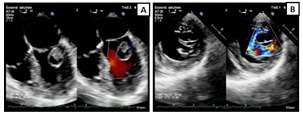

Cardiac magnetic resonance imaging (CMR) provided more accurate tissue characterization: the mass was firmly attached to the ventricular surface of segment P1 of the posterior mitral leaflet, cystic in appearance, with mixed content (solid and liquid) and limited mobility. Cine SSFP sequences showed fluid signal with a small solid component inside; isointense on FSE T1 and hyperintense on FSE T2 and T2 STIR relative to myocardium. There was no perfusion on first-pass gadolinium and no late gadolinium enhancement on PSIR sequence at 10 minutes (Figure 2).

Figure 2. RMC findings: Three-chambers view. A) Cine SSFP sequence: Mass firmly attached to the ventricular surface of segment P1 of the posterior mitral leaflet, cystic in appearance, with mixed content (solid and liquid) and limited mobility. B) FSE T1 sequence: isointense and C) FSE T2 STIR sequence: hyperintense relative to myocardium. D) First-pass gadolinium sequence without perfusion. E) and F) PSIR sequences at early and late gadolinium enhancement respectively without enhancement.

Figure 2. RMC findings: Three-chambers view. A) Cine SSFP sequence: Mass firmly attached to the ventricular surface of segment P1 of the posterior mitral leaflet, cystic in appearance, with mixed content (solid and liquid) and limited mobility. B) FSE T1 sequence: isointense and C) FSE T2 STIR sequence: hyperintense relative to myocardium. D) First-pass gadolinium sequence without perfusion. E) and F) PSIR sequences at early and late gadolinium enhancement respectively without enhancement.